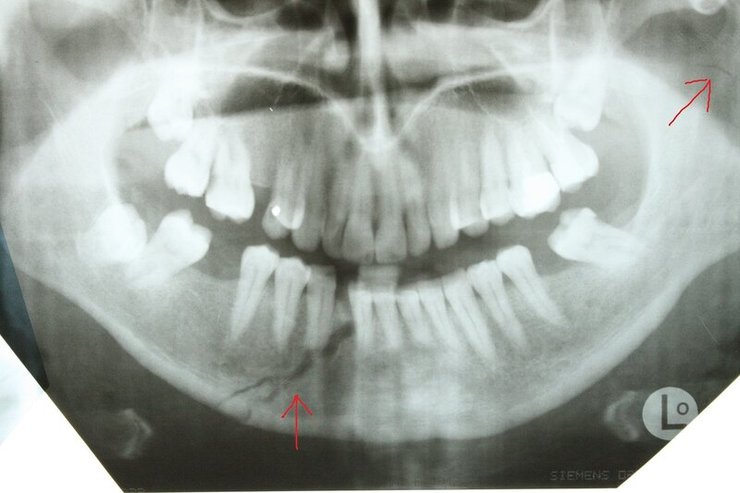

Зламана в результаті ДТП щелепа Адама Кадирова

Щелепа Адама Кадирова

Фото: NIYSO